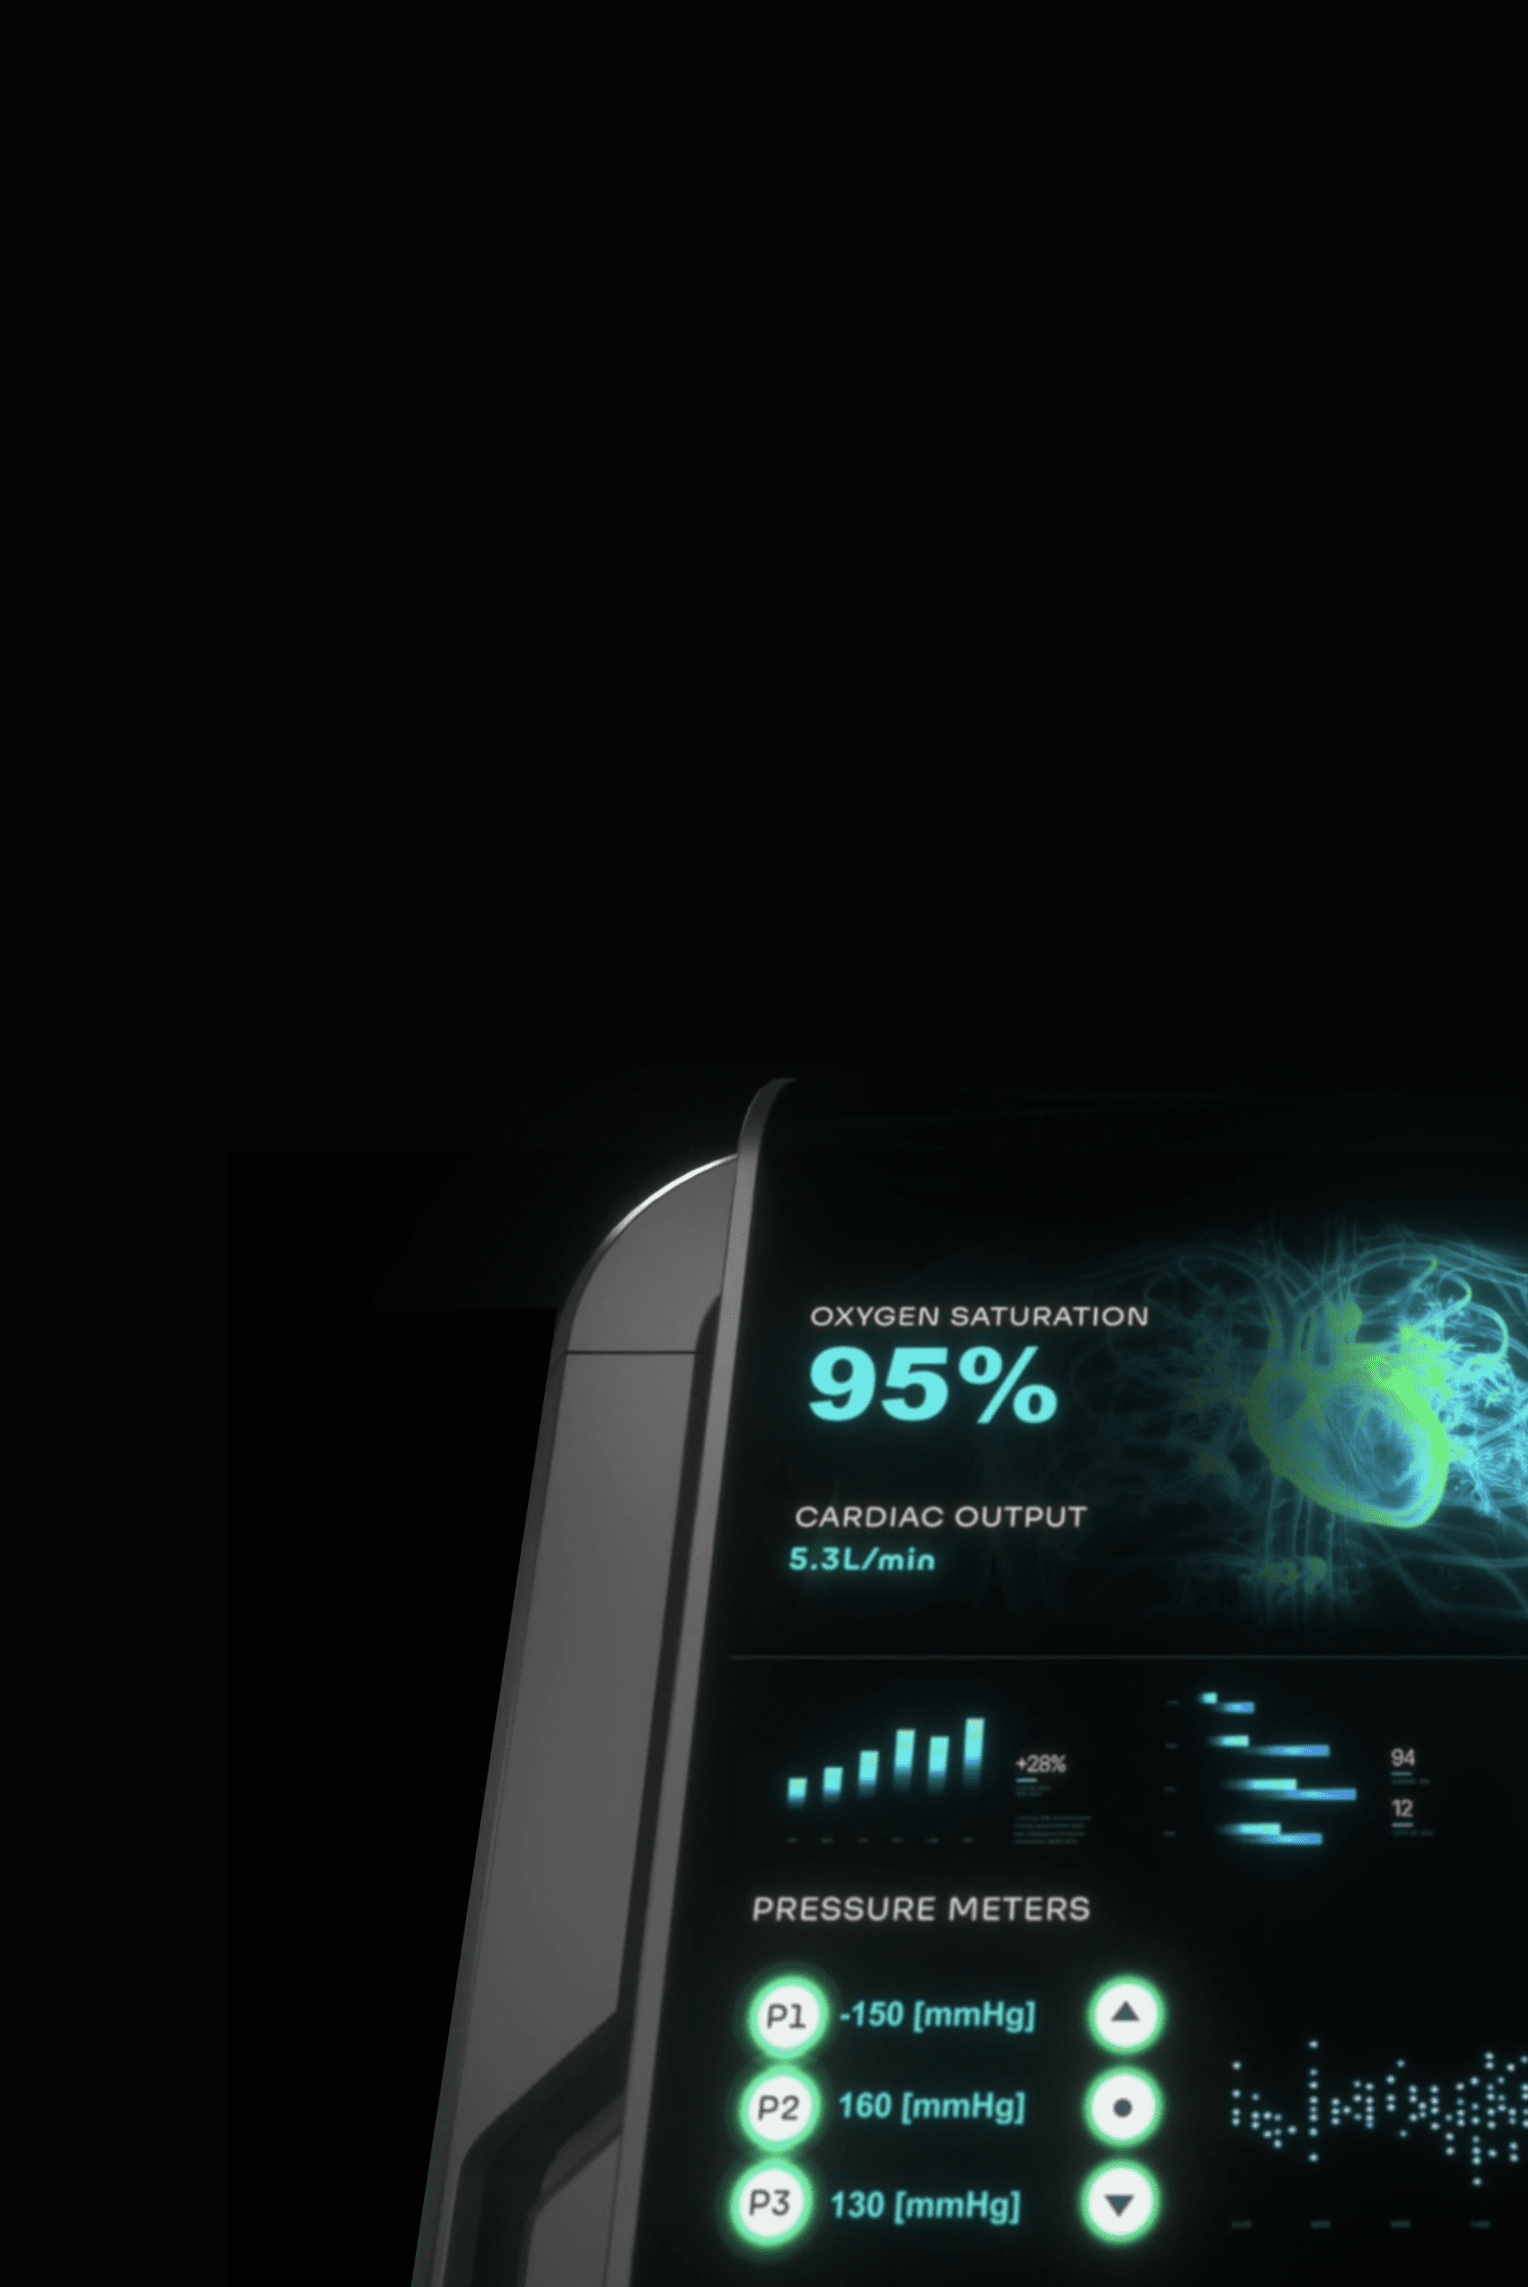

Blood parameters measured continuously and in real-time

Early detection of changes · Provides decision-making

assistance data

The adaptive technology is designed to continuously monitor the patient's blood parameters in real-time, enriching small volumes of blood with oxygen and simultaneously removing carbon dioxide.

HYLA™ Clip-On Blood Lab

Without the need to take intermittent blood samples, the HYLA™ Optic Blood Lab is designed to test, monitor and alert of sudden changes in key blood parameters.

The HYLA™ Blood Sensor is designed to perform real-time analyzing of blood gases, for patients undergoing medical procedures or requiring more frequent patient monitoring.